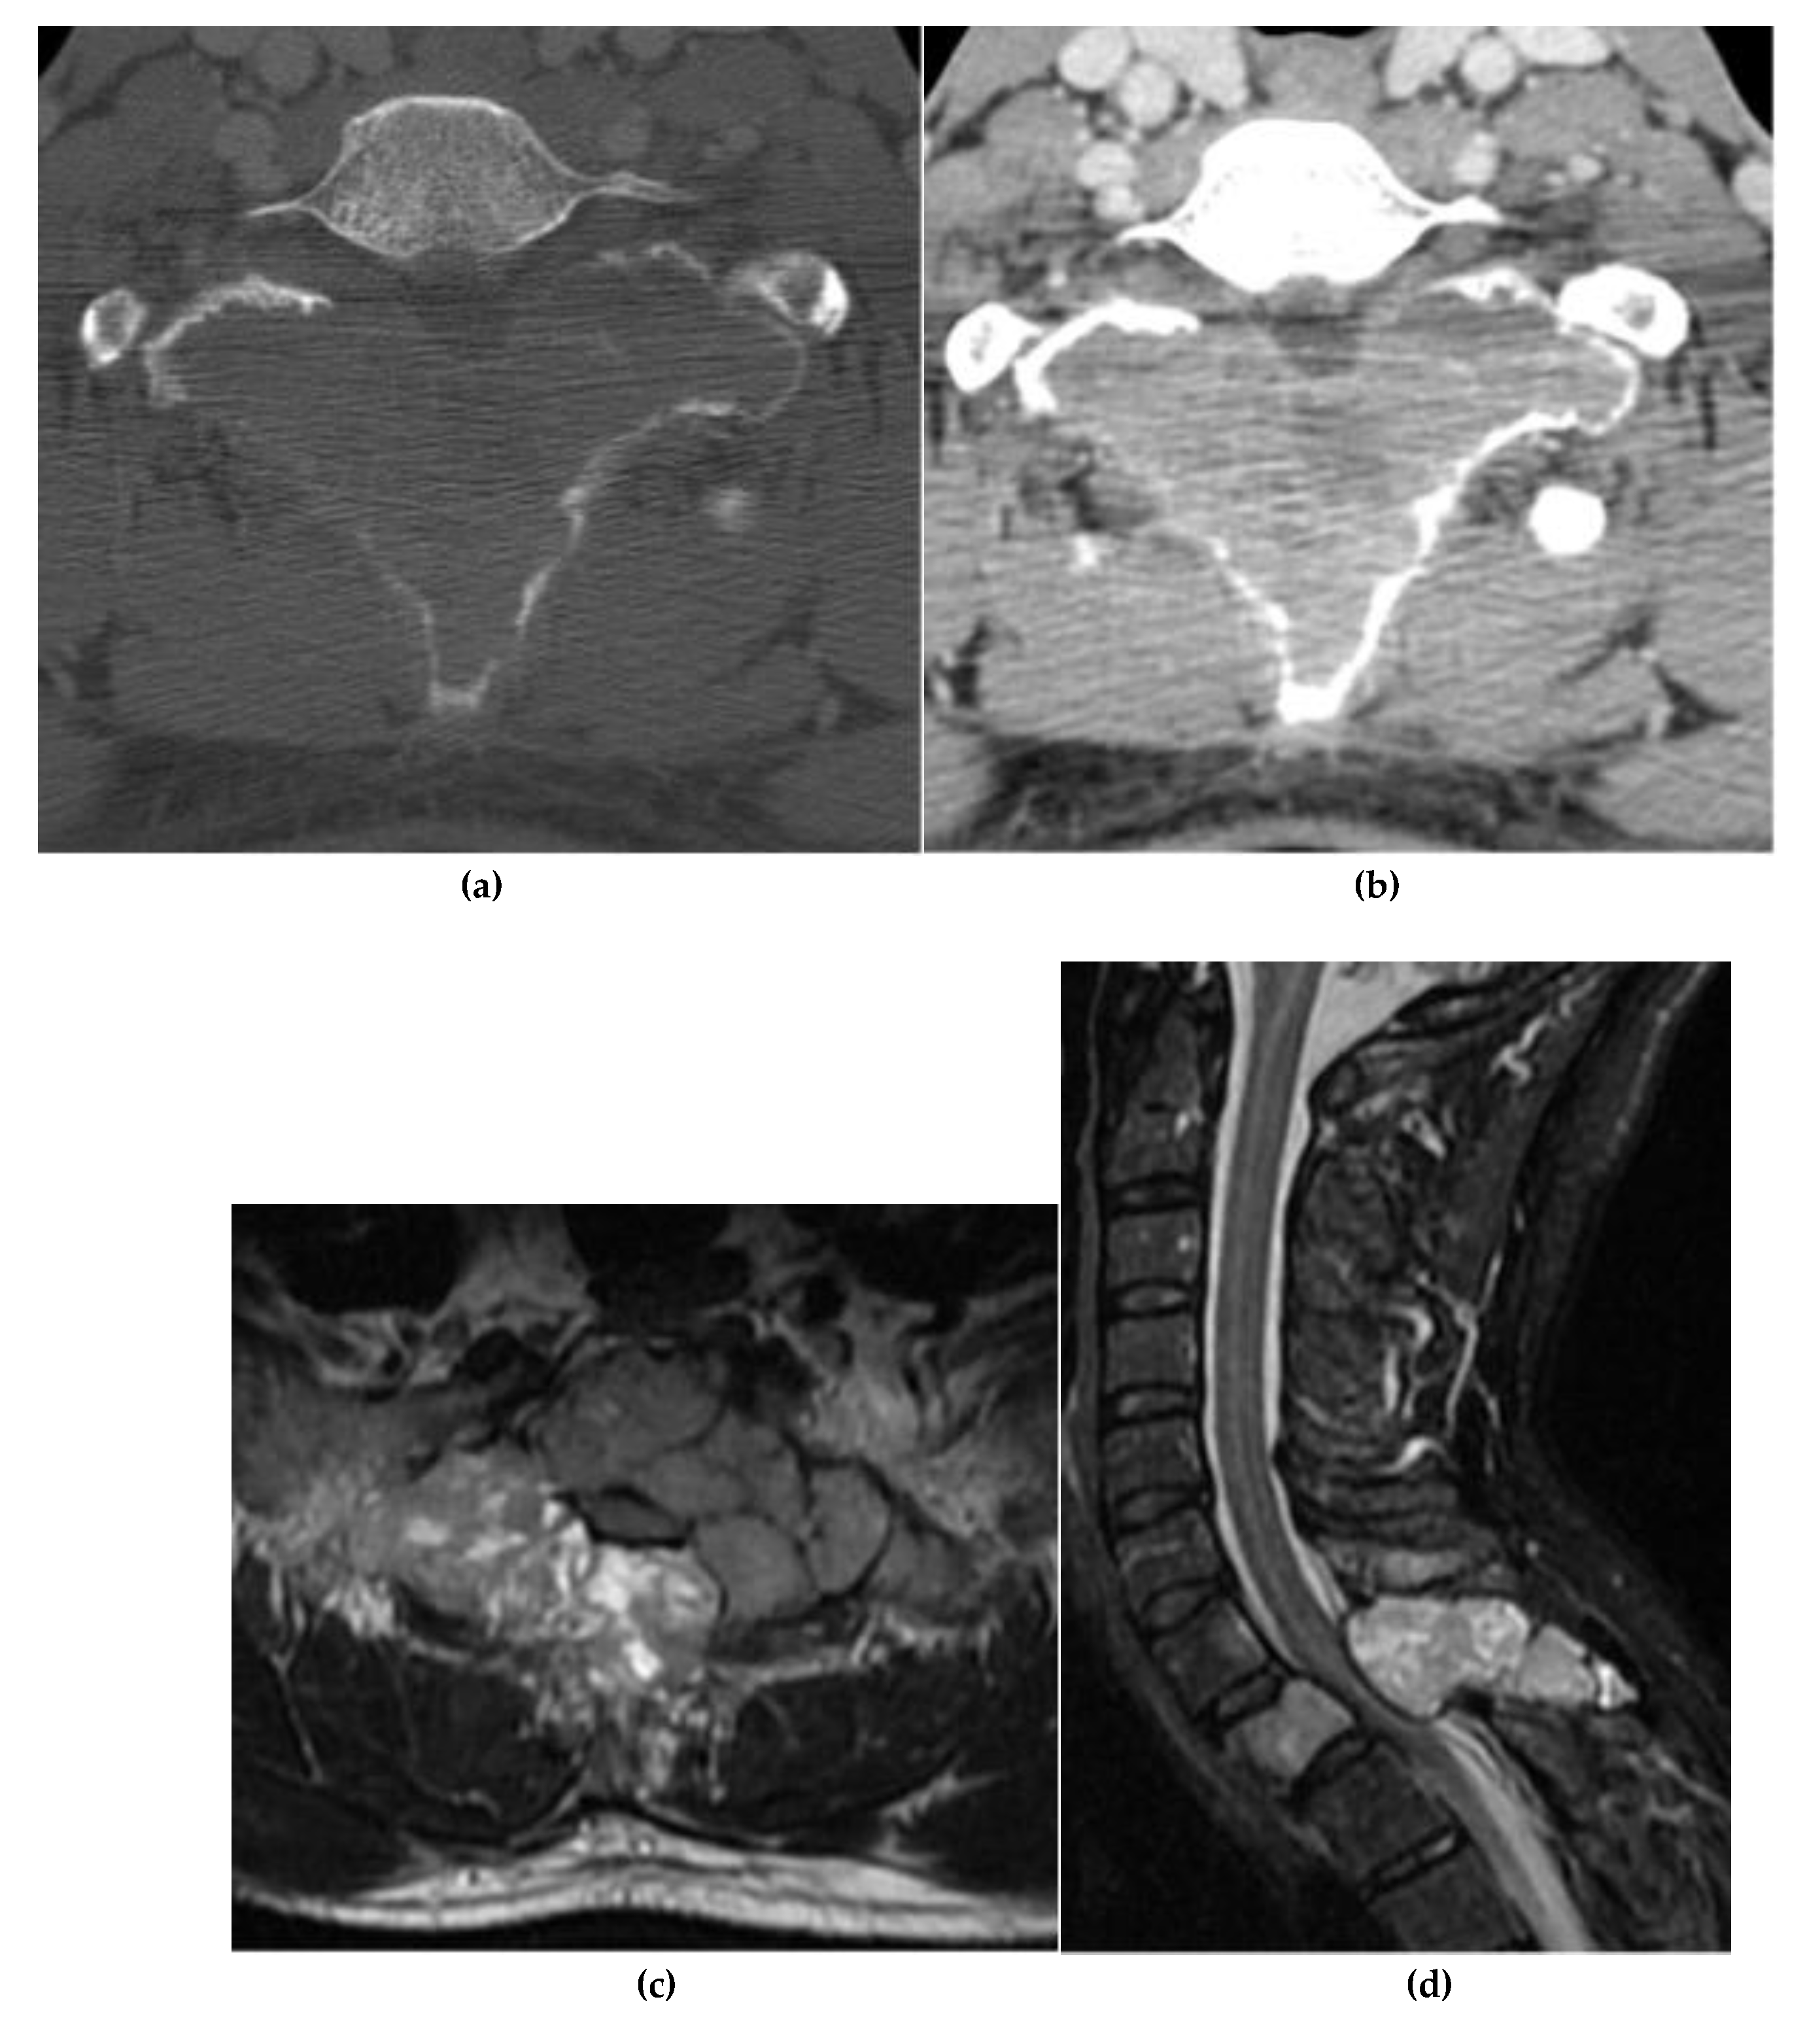

Aneurysmal Bone Cyst